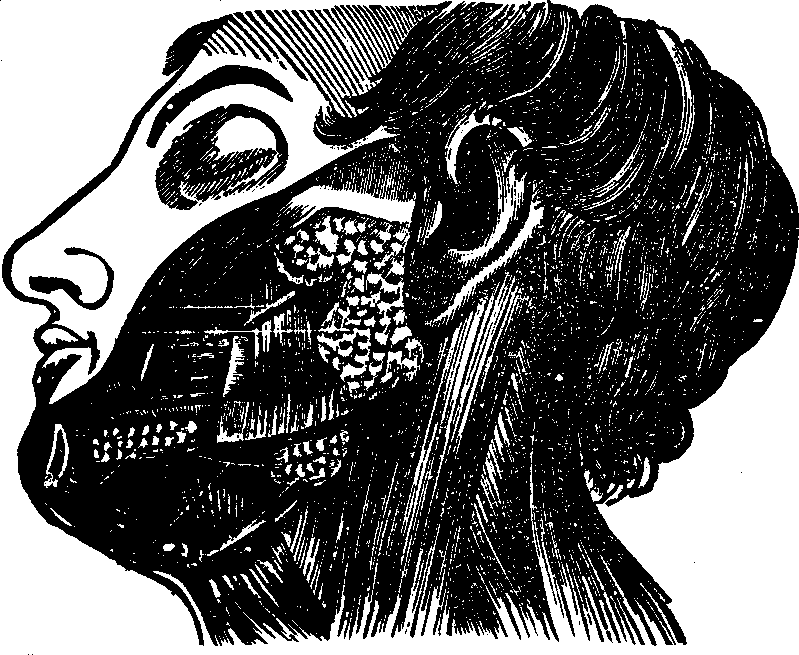

Fig.

27. The salivary glands. The largest one, near the ear, is the parotid

gland. The next below it is the submaxillary gland. The one under the

tongue is the sublingual gland.

The Salivary Glands are six in number, three on each side of the

mouth. Their function is to secrete a fluid called saliva, which

aids in mastication. The largest of these glands, the Parotid, is

situated in front and below the ear; its structure, like that of all the

salivary glands, is cellular. The Submaxillary gland is circular in

form, and situated midway between the [pg 39]angle of the lower jaw and

the middle of the chin. The Sublingual is a long flattened gland,

and, as its name indicates, is located below the tongue, which when

elevated, discloses the saliva issuing from its porous openings.